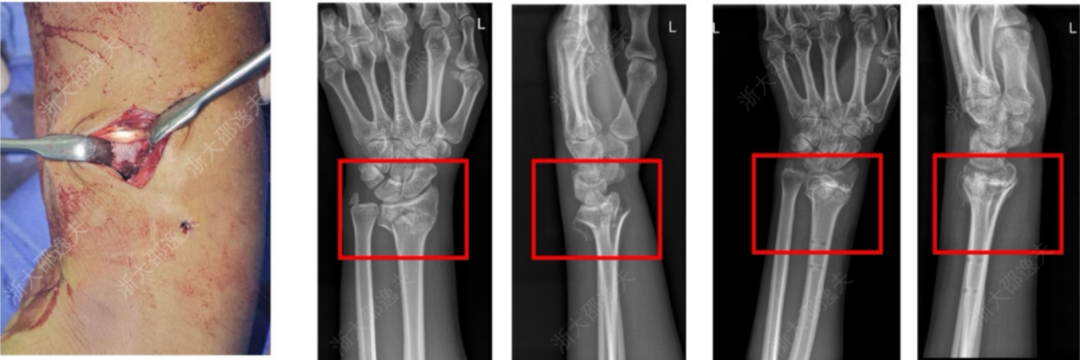

它在多家医院 150 余例受试病例中展现出了良好的安全性和有效性,各项指标达到预设标准。其中一位年轻工人因外伤致腕部粉碎性骨折,为避免传统的钢板内固定手术方案,医生通过一个 2-3 厘米的微创切口注入了“骨 02”,便黏合了碎骨。术后复查显示,患者骨折愈合良好,手腕功能得以恢复。